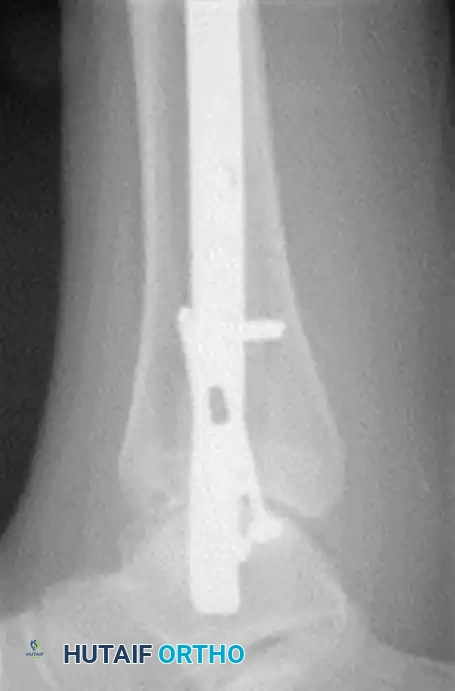

Tibiotalocalcaneal (TTC) Arthrodesis

When the ankle joint is unsalvageable due to severe Charcot destruction, realignment and extended fusion are required. A TTC arthrodesis utilizing a retrograde intramedullary nail provides a load-sharing construct that is biomechanically superior in the neuropathic patient.

Surgical Steps for TTC Nailing:

1. Preparation: The articular cartilage of the tibiotalar and subtalar joints is aggressively debrided down to bleeding subchondral bone.

2. Alignment: The foot is positioned in neutral dorsiflexion, 5 degrees of valgus, and 10 degrees of external rotation.

3. Implantation: A rigid retrograde intramedullary nail is introduced through the plantar aspect of the calcaneus, traversing the talus and into the tibial canal. Multiple locking screws are placed to secure the construct.

FIGURE 85-20 C and D: Postoperative radiographs following successful tibiotalocalcaneal (TTC) arthrodesis with a rigid retrograde intramedullary nail, restoring a plantigrade alignment.